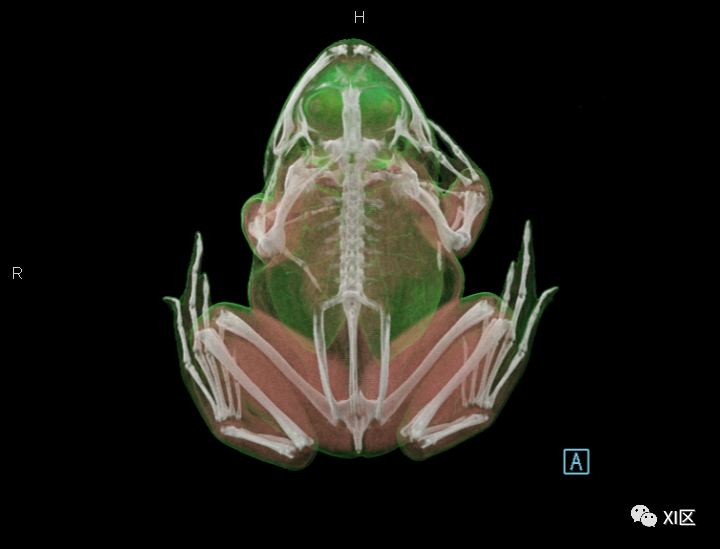

为了了解牛蛙的全身结构

我们给他进行了一次全身CT扫描

并进行了三维重建

先来欣赏一下三维重建的效果

牛蛙的三维重建

牛蛙的三维重建,显示牛蛙肉、肺和骨骼